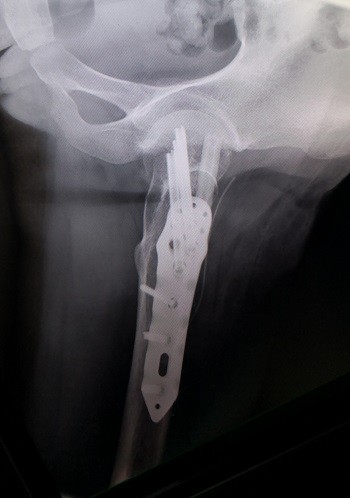

游离腓骨治疗股骨颈不愈合